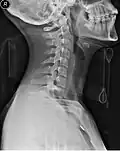

Side view X-ray of the neck with a cervical collar -